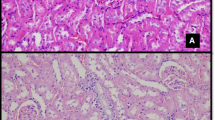

Reducing immunosuppressant-related complications using conventional drugs is an efficient therapeutic strategy. L-carnitine (LC) has been shown to protect against various types of renal injury. In this study, we investigated the renoprotective effects of LC in a rat model of chronic tacrolimus (TAC) nephropathy. SD rats were injected with TAC (1.5 mg · kg−1 · d−1, sc) for 4 weeks. Renoprotective effects of LC were assessed in terms of renal function, histopathology, oxidative stress, expression of inflammatory and fibrotic cytokines, programmed cell death (pyroptosis, apoptosis, and autophagy), mitochondrial function, and PI3K/AKT/PTEN signaling. Chronic TAC nephropathy was characterized by severe renal dysfunction and typical histological features of chronic nephropathy. At a molecular level, TAC markedly increased the expression of inflammatory and fibrotic cytokines in the kidney, induced oxidative stress, and led to mitochondrial dysfunction and programmed cell death through activation of PI3K/AKT and inhibition of PTEN. Coadministration of LC (200 mg · kg−1 · d−1, ip) caused a prominent improvement in renal function and ameliorated histological changes of kidneys in TAC-treated rats. Furthermore, LC exerted anti-inflammatory and antioxidant effects, prevented mitochondrial dysfunction, and modulated the expression of a series of apoptosis- and autophagy-controlling genes to promote cell survival. Human kidney proximal tubular epithelial cells (HK-2 cells) were treated with TAC (50 μg/mL) in vitro, which induced production of intracellular reactive oxygen species and expression of an array of genes controlling programmed cell death (pyroptosis, apoptosis, and autophagy) through interfering with PI3K/AKT/PTEN signaling. The harmful responses of HK-2 cells to TAC were significantly attenuated by cotreatment with LC and the PI3K inhibitor LY294002 (25 μM). In conclusion, LC treatment protects against chronic TAC nephropathy through interfering the PI3K/AKT/PTEN signaling.

Zheng, Hl., Zhang, Hy., Zhu, Cl. et al. L-Carnitine protects against tacrolimus-induced renal injury by attenuating programmed cell death via PI3K/AKT/PTEN signaling. Acta Pharmacol Sin 42, 77–87 (2021). https://doi.org/10.1038/s41401-020-0449-8